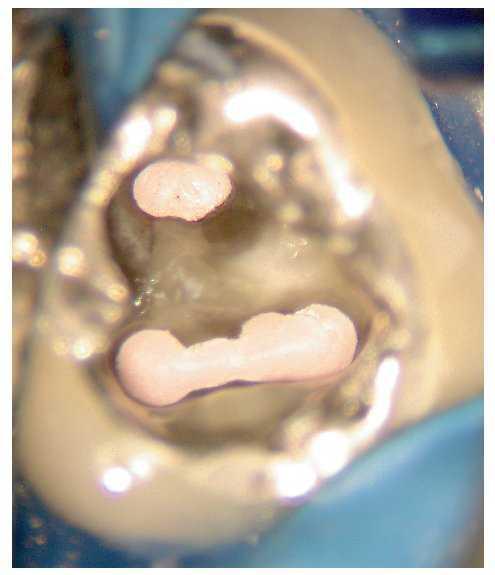

Figura 2e. Situación después del retratamiento de los conductos principales. Se aprecia con claridad el tejido existente en el istmo mesial.

Figura 2f. Situación después de la preparación completa del istmo mesial coronal. Se pudo palpar otro istmo en el tercio medio de la raíz mesial a través del que fluyó líquido de irrigación. Se preparó este istmo mediante instrumentos ultrasónicos.